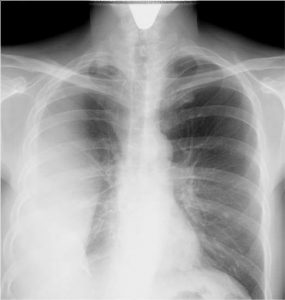

- Полипозиционная рентгенография грудной клетки (в трех проекциях).

- Рентгеноскопия легких.

- Компьютерная томография легких (КТ).

- Ультразвуковое исследование плевральной полости (УЗИ).

Симптомы заболевания

Симптоматика и другие аспекты осумкованного плеврита могут различаться в зависимости от его вида, который определяется с помощью рентгена. Например, выделяют апикальный тип, при котором жидкости скапливаются вверху легкого. Парокостальный вариант отличается тем, что скопление упирается в поверхность ребер широкой частью. Выделяют междолевой плеврит, при котором экссудат откладывается в междолевых щелях. В этом случае на рентгене видна четкая картина – проявление болезни напоминает вытянутую тень. Базальный вид патологи характеризуется близким расположением выпота и диафрагмы.

Обнаружить парамедиастинальный вид, как правило, можно только с помощью рентгена, хотя, в случае крупных скоплений жидкости, возможны загрудинные боли, появление проблем с дыханием, сиплость голоса, а также нередко набухают вены на шее.

Если осумкованный плеврит был сильно запущен, иногда требуется проведение компьютерной томографии. Эта методика во многом схожа с рентгеном, однако она дает более точное изображение и представление о распространении опухолевых процессов.

В результате течения заболевания могут произойти изменения в бронхах или сосудах. Подобное отслеживается специалистами с помощью таких рентгенов как бронхография или ангиопульмонография.

При диагностике плеврита, для успешного лечения важно не только узнать о расположении и течении заболевания, но и определить характер экссудата. Это делается с помощью ультразвукового обследования плевральной полости, а также взятия пункции и биопсии.

Помимо рентгена, при обследовании органов в грудной клетке может применяться диагностическая тораскопия. В конечном итоге происходит дифференциальная диагностика, которая помогает исключить присутствие патологий вроде кисты легкого или злокачественных образований.

Физиотерапия обычно включает в себя дыхательную гимнастику и электрофорез, также применяется ультразвук. По результатам рентгена может быть назначено дренирование плевральной полости.

Для того чтобы предотвратить развитие и последующее лечение плеврита осумкованного, нужно уделять внимание профилактике. Она связана со своевременным выявлением первичных заболеваний. В частности, при появлении симптомов пневмонии нужно проходить рентген (но не слишком часто).

Аускультация помогает выявить ослабление дыхания в районе поражения наряду с шумом трения плевры. В рамках перкуссии определяют притупление звуков над местом жидкостного скопления. Инструментальные методики диагностики дают возможность установить точный диагноз:

- Зачастую проводится при осумкованном плеврите рентген грудной клетки и легких. Снимок при этом делается в нескольких проекциях. Крупный осумкованный плеврит на рентгене обычно виден в форме затемнения в том или ином районе плевральной полости. По локализации определяют вид плеврита.

- Дополнительно проводится ультразвуковое исследование. На таком исследовании можно определять даже самые небольшие объемы жидкости.

- Еще одной методикой диагностического исследования является компьютерная томография. Ее проводят при запущенном плеврите, она дает более точное представление о свойствах и характере патологического процесса. Но эту процедуру проводят далеко не во всех медицинских учреждениях, а стоимость у нее достаточно высокая.